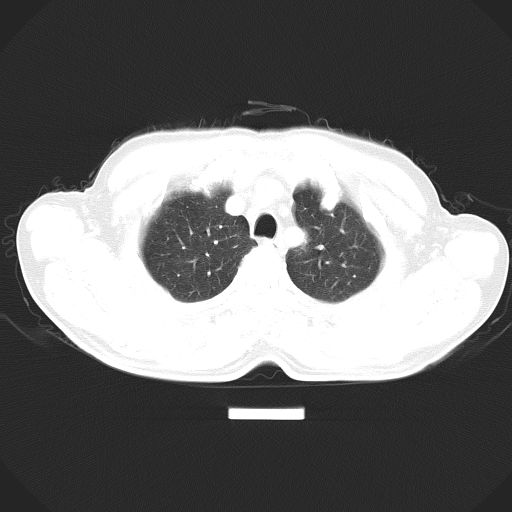

以下是引用心路寻觅在2010-3-1 10:23:00的发言:[br]1、考虑左肺上叶周围型肺癌[br]2、右上肺陈旧性病灶。[br][br][本贴已被 心路寻觅 于 2010-3-1 10:40:18 修改过]

以下是引用shuiyuan在2010-3-1 10:45:00的发言:[br]考虑左肺上叶中心型肺癌伴阻塞型炎症,邻近胸膜受侵。